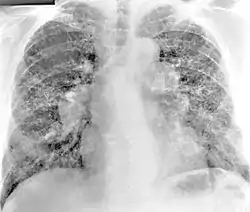

Los hallazgos de la radiografía de tórax de beriliosis son inespecíficos. En las primeras etapas de la enfermedad, los hallazgos radiográficos suelen ser normales. En estadios posteriores se ha informado fibrosis intersticial, irregularidades pleurales, linfadenopatía hiliar y opacidades en vidrio deslustrado . Los hallazgos de la TC tampoco son específicos de la beriliosis. Los hallazgos que son comunes en las tomografías computarizadas de personas con beriliosis incluyen nódulos parenquimatosos en etapas tempranas. Un estudio encontró que las opacidades en vidrio esmerilado se observaron con más frecuencia en la tomografía computarizada en la beriliosis que en la sarcoidosis. En estadios posteriores, linfadenopatía hiliar, fibrosis pulmonar intersticial y engrosamiento pleural.